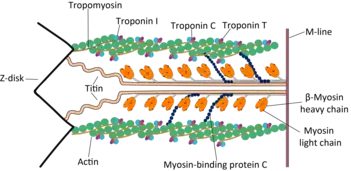

Troponin C is a protein which is part of the troponin complex. It contains four calcium-binding EF hands, although different isoforms may have fewer than four functional calcium-binding subdomains. It is a component of thin filaments, along with actin and tropomyosin. It contains an N lobe and a C lobe. The C lobe serves a structural purpose and binds to the N domain of troponin I (TnI). The C lobe can bind either Ca2+ or Mg2+. The N lobe, which binds only Ca2+, is the regulatory lobe and binds to the C domain of troponin I after calcium binding.